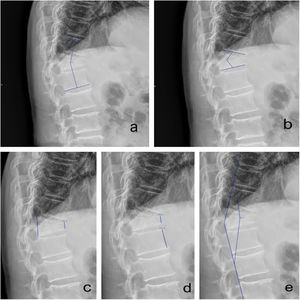

Las medidas radiológicas utilizadas para valorar la deformidad sagital producida por la fractura, la corrección realizada con la intervención quirúrgica y su evolución en el tiempo han sido (fig. 4):

- •

Ángulo fracturario: ángulo formado entre platillo superior de vértebra superior a fracturada y platillo inferior de vértebra inferior a fracturada.

Deformidad cifótica: ángulo obtenido entre platillo inferior de vértebra superior a fracturada y platillo inferior de la vértebra fracturada.

Porcentaje compresión (Í. Berg): cociente entre altura de pared anterior de vértebra fracturada y pared posterior de vértebra fracturada, multiplicado por 100.

Porcentaje de acuñamiento: cociente entre altura de pared anterior de vértebra fracturada y pared anterior de vértebra inferior a la fracturada, multiplicado por 100.

Ángulo de deformación: ángulo formado por la intersección de la línea siguiendo la pared posterior de vértebras superiores a la fracturada con línea de pared posterior de vértebras inferiores a la fracturada.

Resultados radiológicosEl ángulo fracturario medio en el grupo de corpectomía fue 29,52° en el preoperatorio, con corrección a 7,54° grados en el postoperatorio inmediato, 10,22° a las seis semanas y 14,52° a los tres meses. En el grupo de la vertebroplastia 17,2° preoperatorios, con corrección a 7,4° en el postoperatorio inmediato, 12,39° a las seis semanas y 14,45° a los tres meses (fig. 5a).

El índice sagital inicial en el grupo de corpectomía fue de 17,48°, 1,22° en el control posquirúrgico inmediato, 1,12° a las seis semanas y 2,12° a los tres meses. En el grupo de vertebroplastia la angulación inicial era menor, 13,83° y la corrección obtenida de 9° con un índice postoperatorio inmediato de 4,51°, a las seis semanas se mantenía en 4,82° y a los tres meses fue de 5,32° (fig. 5b).

El porcentaje de compresión o Índice de Berg fue en los pacientes a los que se les realizó corpectomía de 35,24% antes de la intervención, alcanzando el 79,88% tras la cirugía, 71,16% a las seis semanas y 62,9% a los tres meses. En el grupo de vertebroplastia al momento de la fractura presentaba una compresión de 42%, alcanzando el 69,45% tras la cirugía. A las seis semanas fue de 63,6% y a los tres meses de 57,64% (fig. 5c).

El porcentaje de acuñamiento presentó una evolución similar al de compresión. En el grupo de corpectomía el índice prequirúrgico era de 27%, 74,98% en el postquirúrgico inmediato, 69,58% a las seis semanas y 68% a los tres meses. Los que recibieron vertebroplastia tenían una media previa a la intervención de 37,27%, tras la misma el porcentaje fue de 63,58%, a las seis semanas 57% y a los tres meses 53,54% (fig. 5d).

El ángulo de la deformación inicial en el grupo de corpectomía fue de 22,25°, tras la cirugía de 9,62°, a las seis semanas de 11,47° y a los tres meses de 16,6°. En el grupo de vertebroplastia inicialmente medía 17°, en el postquirúrgico inmediato 8,81°, a las seis semanas 13,19° y a los tres meses de 17,63° (fig. 5e).